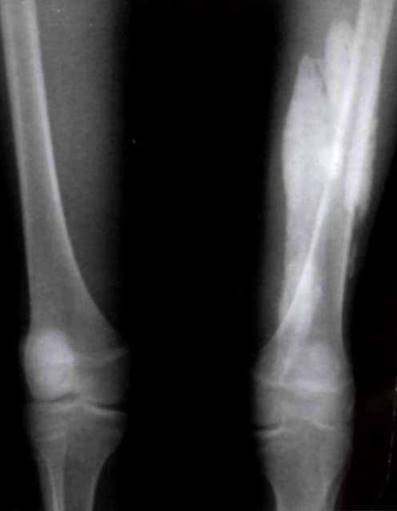

Рис. 21-6. Деформация коленных и голеностопных суставов.

Рис. 23-2. Типичное поражение суставов при ювенильном спондилоартрите - артриты коленных, голеностопных, суставов предплюсны.